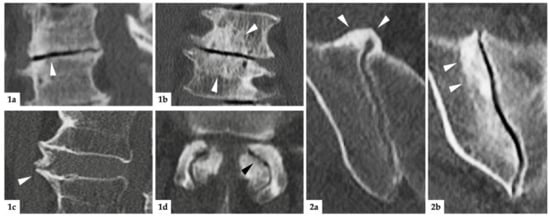

A radiologist with 5 years of clinical experience and expertise in musculoskeletal imaging (K.Z.) scored all images in random order, blinded to clinical data. Images were read using a dedicated software (Horos v3.3.6, The Horos Project, public license). SIJ degeneration was assessed as periarticular sclerosis of at least 2 mm width and/or osteophytes at the ventral or dorsal aspect of the joint. A more detailed description of this assessment has been published in detail elsewhere []. The degeneration of the lumbar spine was assessed separately for spinal segments L1/L2 through L5/S1; in each segment, the presence or absence of disc degeneration (defined as: marked narrowing of the intervertebral space and/or vacuum phenomenon of the disc), endplate degeneration (defined as: marked sclerosis of >3 mm), spondylophyte formation, and osteoarthritis (OA) of the facet joints (defined as: narrowing of the joint space and presence of osteophytes around the facet joints) was noted. Imaging examples for all instances of degeneration are provided in Figure 2. To assess inter-reader agreement, a random sample of 40 patients was assessed by a junior radiologist (V.K.), applying the same scoring system.

Figure 2. Imaging examples. (1): Degenerative lesions of the lumbar spine; (1a) = sagittal reconstruction: white arrowhead marks discal vacuum phenomenon and narrowing of intervertebral space; (1b) = coronal reconstruction: white arrowheads mark sclerosis of endplates; (1c) = sagittal reconstruction: white arrowhead indicates spondylophyte; (1d) = axial reconstruction: black arrowhead marks intraarticular vacuum phenomenon. Additionally, note the extensive sclerosis and joint space irregularities from OA of the facet joints. (2): degenerative lesions of the SIJ; (2a) = axial reconstruction: ventrally located, bridging osteophytes of the right SIJ marked with white arrowheads; (2b) = oblique-coronal reconstruction: extensive sclerosis around the joint (white arrowheads).